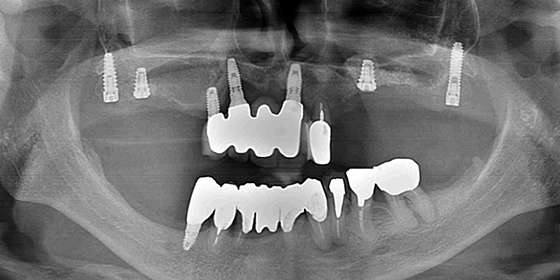

患者様は、他院で上顎の骨を増やすサイナスリフト手術を受けましたが、骨ができず、当院にて再度サイナスリフトを行いました。その後、以前から存在していたインプラントと連結しました。

右側の上顎洞は感染を起こし、あまり骨ができませんでしたが、骨のある場所をCTで探して、コンピュータサージカルガイドを用いて、ピンポイントでベストな位置にインプラントを埋め込みました。

半年後

すべてのインプラントが骨と結合しているのを確認しました。前医が治療した上顎前歯のブリッジは取り外し、今回埋めたインプラントと連結することにしました。